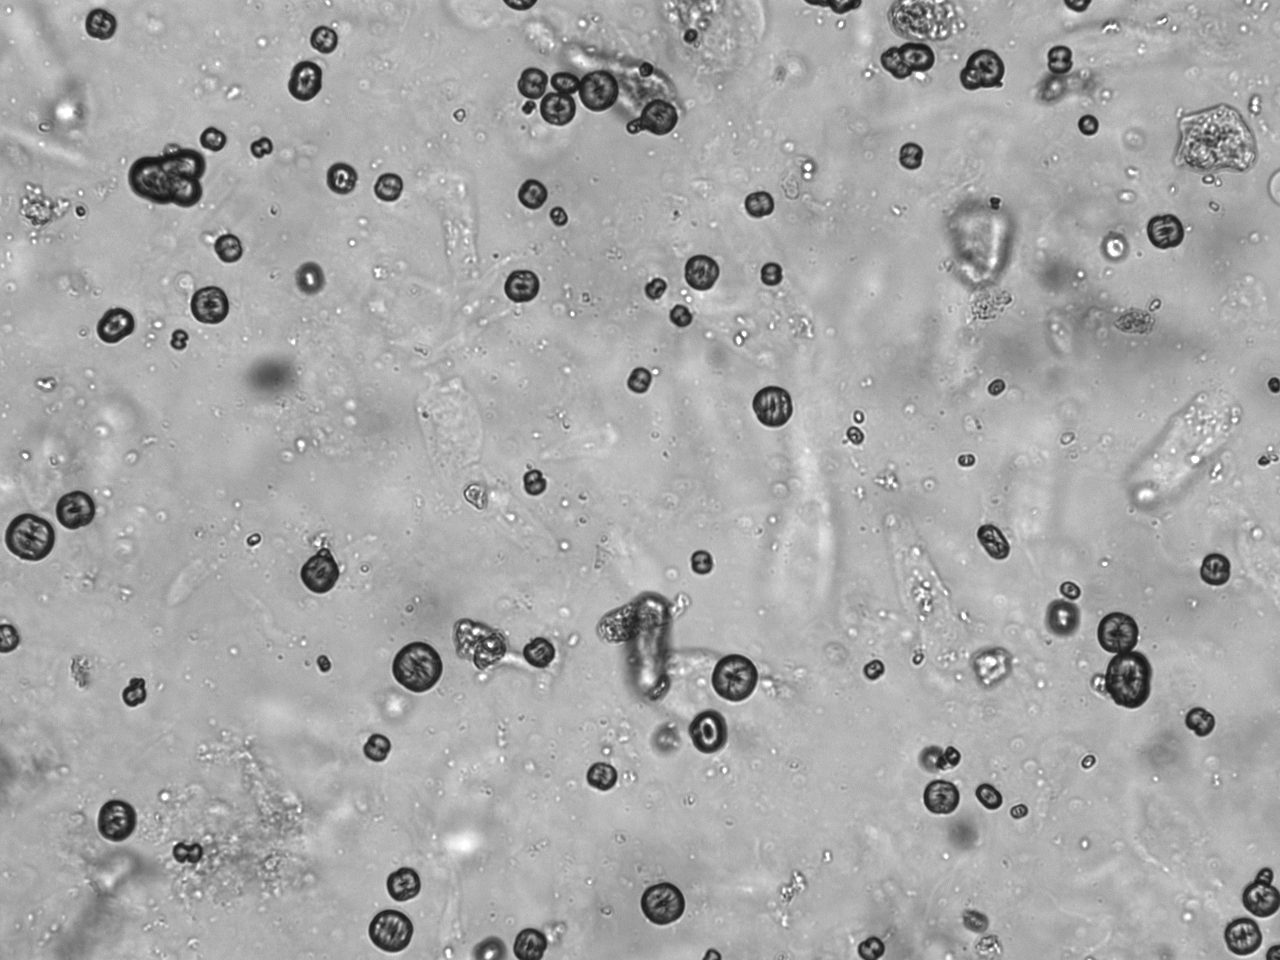

Urin-Feature: Leucinkugeln